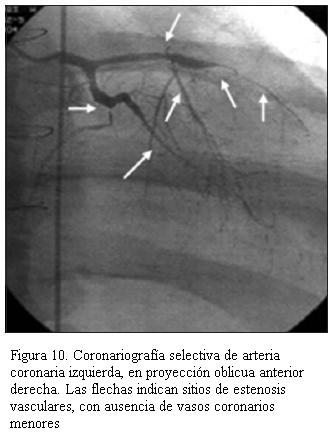

Desde la utilización de everolimus a partir del año 2004 en 43 pacientes, no hemos tenido nuevos casos de enfermedad vascular del injerto (EVI) y en aquellos que ya la presentaban, esta no ha aumentado por lo menos hasta el momento. Cabe destacar que se realiza coronariografía. Ningún paciente tiene ecografía intraluminal. Dos pacientes, un adolescente de 14 años de edad con siete años de trasplantado (figura 10), y un paciente adulto luego de cinco años de trasplantado, presentaron EVI; ambos requirieron angioplastia coronaria con colocación de stent como puente al retrasplante, el cual se efectuó a los seis meses en el primer caso y a los dos años en el segundo. Actualmente llevan siete y tres años, respectivamente, posretrasplante, con buena evolución sin evidencia de rechazo ni EVI.